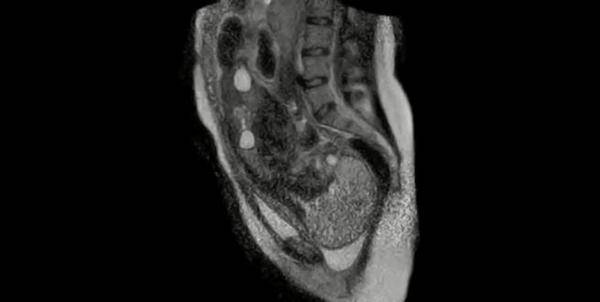

За да можат да ја проучат интеракцијата на фетусот и мајчината карлица, истражувачите во Породилиштето во Берлин во живо го гледале породувањето на една жена со помош на магнетна резонанса. Снимката е направена во 2010 но дури сега е објавена во јавноста. Ова е прва ваква снимка во светот.

На снимката се гледа напорот ој го дава родилката, контракциите пред самото породување. Потоа снимката е прекината за да не се оштети слухот на новороденчето поради јакиот звук кој го произведува магнетната резонанса како и јаките магнетни полиња кои можат да ги уништат рскавичните делови на телото кај новороденчето.